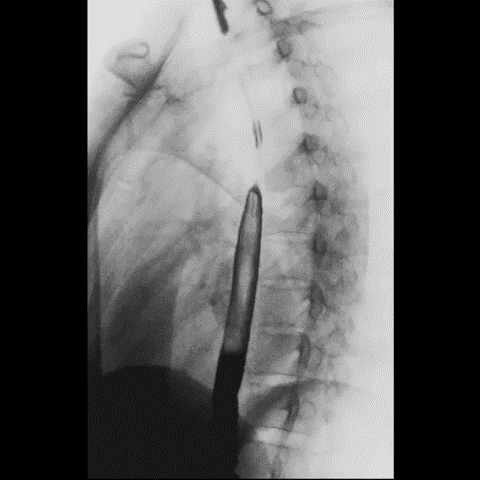

● 全自动全景智能拼接

系统采用像素级灰度值拟合校正技术,全自动完成全景拼接,图像拼接过程稳定、顺畅、精准,为医院骨科整形及术后效果评估提供重要参考依据。